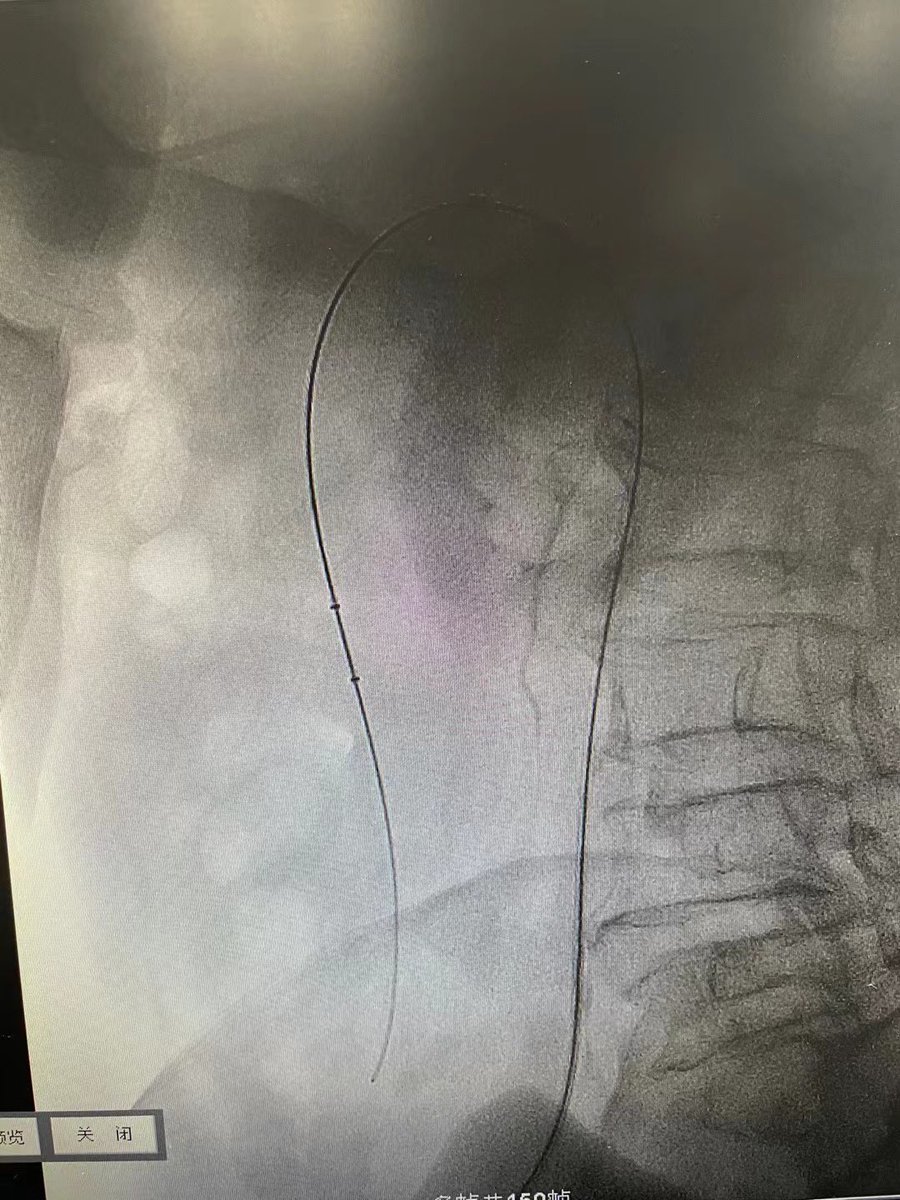

39 yo F on #OCPs. Acute Lt. LL pain n swelling, extensive #DVT, CT confirms #MayThurner #syndrome. Thrombolysis, Thrombectomy done using #AngioJet, followed by #venoplasty & stenting. #IRad is #OneStopShop! @SIRspecialists @pakIRSP @cirsesociety @rahilkassamali @drsaadrehman 1/2